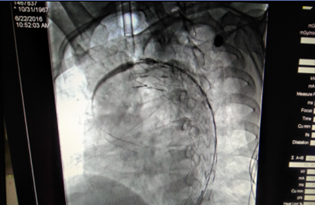

術(shù)中(釋放支架)

術(shù)后(見主動(dòng)脈血流規(guī)則,治療效果良好)

“微創(chuàng)腔內(nèi)治療技術(shù)給患者帶來了福音?!蔽河钫f。手術(shù)僅需行腹股溝部的小切口,在X線監(jiān)視屏監(jiān)測(cè)下通過微創(chuàng)介入的方法將覆蓋人工血管的金屬支架精確植入到有問題的血管,從而將血流與問題管壁隔絕。手術(shù)難度很大,風(fēng)險(xiǎn)極高,醫(yī)生操作需要非常謹(jǐn)慎,支架需精確植入到病變位置。手術(shù)能實(shí)現(xiàn)與開腹手術(shù)相同的治療效果,但避免了開腹手術(shù)引起的創(chuàng)傷及相關(guān)并發(fā)癥,術(shù)后恢復(fù)時(shí)間也遠(yuǎn)遠(yuǎn)短于外科手術(shù),一般2-3天即可。